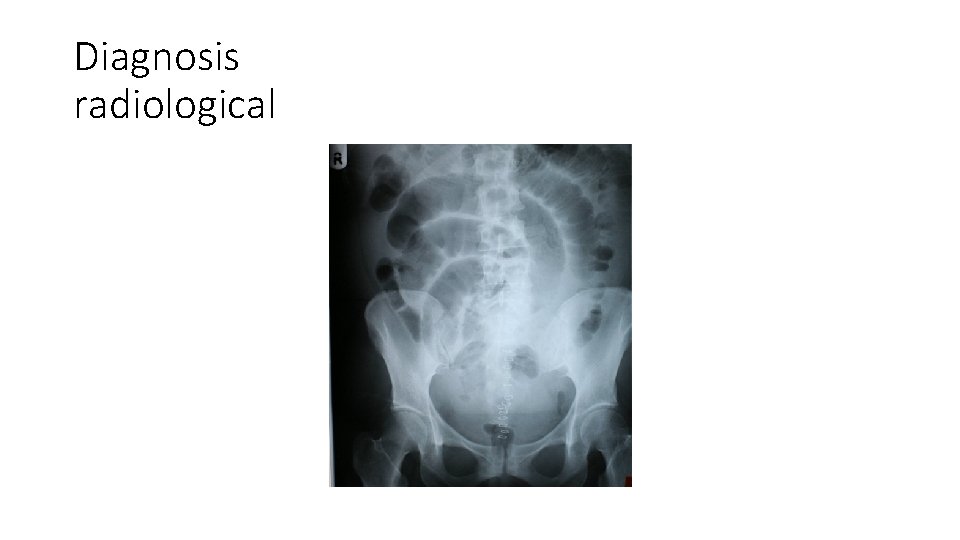

Diagnosis radiological